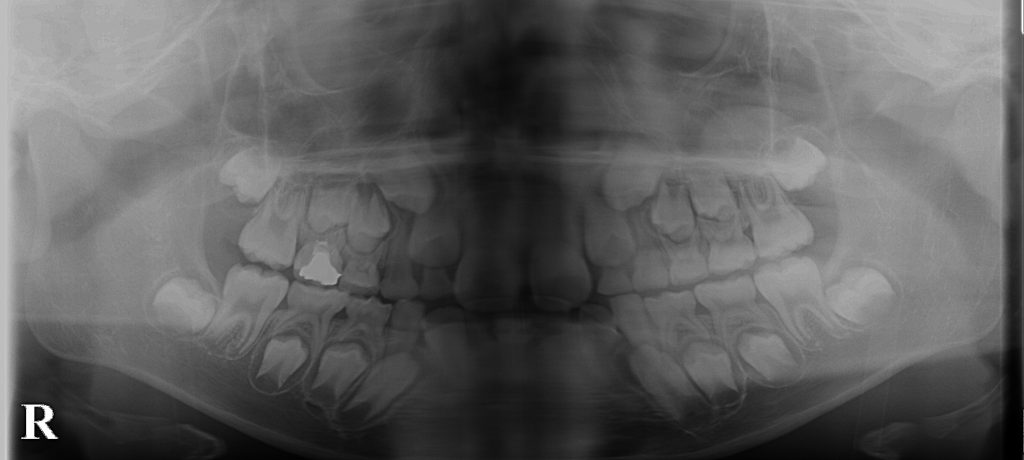

こむら小児歯科・矯正歯科で経過観察してきたケースです。

上の犬歯の位置が悪かったのですが、最終的には問題なく生えてきました。

どんなケースでも矯正治療が必要というわけではなく、正しい診断の元に経過観察することも大切です。

埋まっている上の犬歯を引っ張らなくても このようにきれいに生えてくる事もあります。